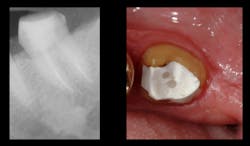

If more than one-half of the tooth’s coronal portion is missing, increasing the antirotational and strength characteristics of the coronal buildup is mandatory by placing retentive metal pins. Pure titanium pins (Filhol Filpin) are ideal because they do not crack the tooth structure, which is usually the case with more rigid stainless steel or titanium alloy pins (figure 4).The submerged post length should be at least one-half of the bony supported length of the tooth. This recommendation is contrary to some suggestions to make the posts extend down three-quarters of the root length. The one-half recommendation, when properly done, is as retentive as placing the post deeper, and it prevents root perforations.